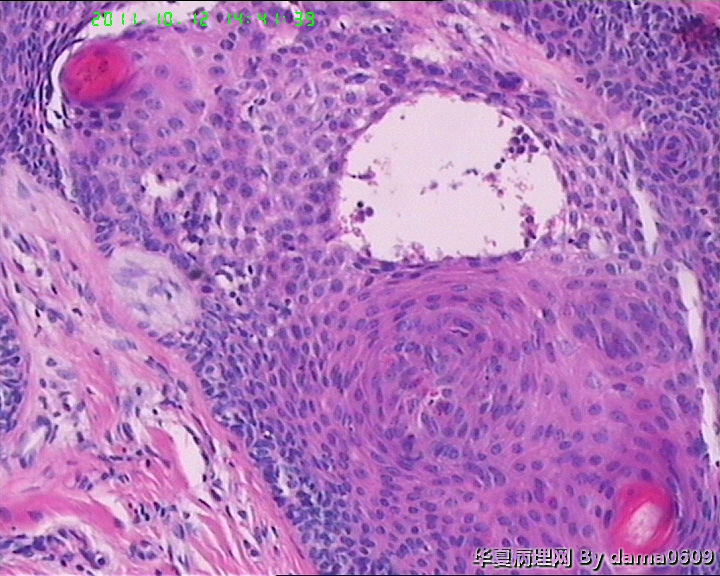

女,42岁,右眼外上方皮下肿物4年。

送检:椭圆形肿物,v:0.5x0.5x0.4cm,实性,灰白色,质软。

• 眼角旁皮下肿物,不会了啊!!图3

图3

毛发腺瘤

皮肤及附属器的肿瘤学生见得少,这一例发病部位和大体上符合“毛发上皮瘤”,但静下上好像要求由两层基底样细胞条索样排列和增生的间质构成,具体记不清了,也不知道对不对,我这例不见那样的典型结构啊!!

镜下大部分都是毛囊结构,要考虑毛囊痣。